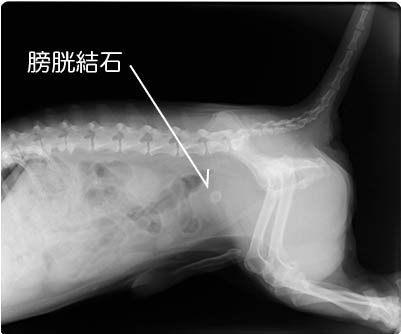

犬 膀胱結石. 犬の尿石症 コーギーの1例 手術で膀胱結石を摘出しました 尿石症とは? 尿石症(尿路結石)とは、尿路である腎臓(腎盂)、尿管、膀胱または尿道のいずれかに結石が形成される病気です。 猫の特発性膀胱炎(FIC) 猫のおしっこに関する病気を総称して猫下部尿路疾患(FLUTD)と呼びます。 その症状として、血尿、頻尿、排尿時に痛がる、ト 排尿障害 〝何度. 膀胱と腎臓を繋ぐ管に出来る尿管結石 3膀胱に出来る膀胱結石 4尿道に石が詰まる尿道結石 犬の結石には4種類あり原因となる野菜・食べ物は異なる. 犬の膀胱・尿道結石の一例 小手指ペットクリニック 16年11月28日 8才のワンちゃんが、昨日から尿が出ずに元気がないとのことで来院されました。 レントゲンを撮ると、膀胱内に7個程度、尿道に3個(ペニス先端から10cmに2個、13cmに1個)の石が.

犬の膀胱結石とは、尿をためる袋とも言うべき膀胱に結石を生じた状態を言います。 膀胱 (ぼうこう)とは腎臓から送られてくる尿を一時的に溜める袋状の器官であり、左右の腎臓から尿管を通して尿を受け取り、尿道を通して体外に排出します。 膀胱結石は尿路結石の中で最も発症頻度が高く、多くは 膀胱炎 に引き続いて起こります。 尿道が短くて細菌の進入. うえの犬猫病院は犬 リンク 採用情報 お問合せ 症例紹介 膀胱結石 膀胱結石とは 膀胱結石は膀胱炎や細菌感染、尿路閉塞の原因になります。特に尿路閉塞が危険で、結石が排尿路に詰まると急性腎不. Case42 膀胱結石の犬の1例 血尿と頻尿を主訴に来院した8歳の雄のワンちゃんです。 4ヶ月前にも同様の症状がありましたが抗生剤の投与で改善しました。 今回も同様の治療を試みましたが間欠的に血尿が続き、再発ということもありレントゲンと超音波検査を実施しました。 レントゲン検査では膀胱領域に数ミリの結石を認め、超音波検査でも複数の結石が確認され.

犬 膀胱結石・尿道結石 チワワ 10歳11ヶ月齢 去勢オス 71kg 頻尿と血尿、排尿障害を主訴に来院 腹部と陰茎の触診検査にて結石症が疑われたため、 レントゲン検査を行い、膀胱結石および尿道結石、腎臓結石と診断した 尿道内にぎっしりとつまった結石は、カテーテルにて膀胱内に押し戻し、膀胱切開にて膀胱結石を摘出した 腎臓結石はに対する外科処置は、腎臓. 犬の膀胱結石 更新日時: ミニチュアダックスフンド、オス (去勢)、11歳 《主訴》血尿、排尿しづらい (少量ずつしか出ない) 《検査》①腹部レントゲン検査 膀胱に結石と思われる不透過性陰影を多数確認 ②腹部超音波検査 膀胱内に結石と思われるシャドーを引く高エコー物を多数確認 ③尿.